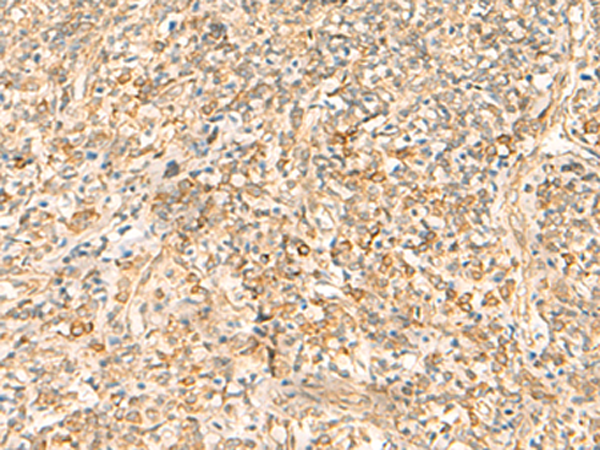

分类: 科研抗体货号: P02908别名: AGS3应用: WB,IHC反应种属: Human, Mouse, Rat